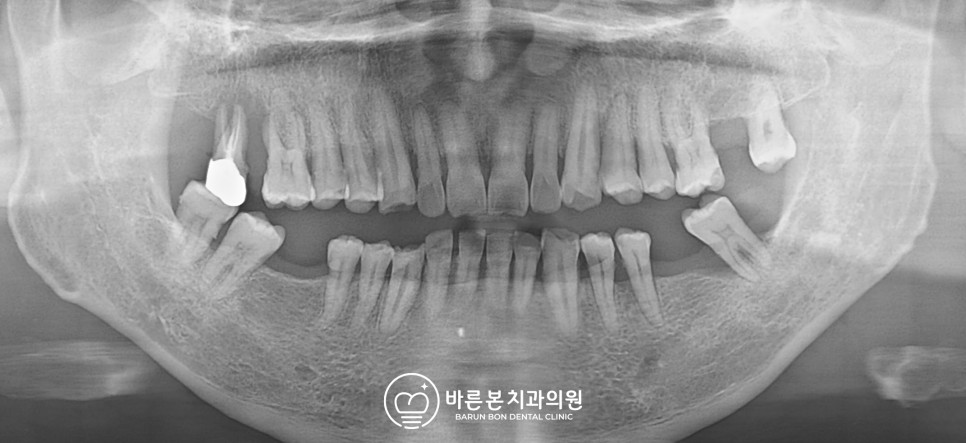

초진: 구강 사진과 파노라마 뷰 소리가 난 치아 상태를 보기 위해 파노라마 사진을 촬영해 봤습니다.

<21.11.29 촬영>

사진상 왼쪽 어금니에 이상이 보였는데, 치조골 소실이 심해 정출현상이 나타나고 있었습니다.

전체적으로 자연치가 소실된 부분이 많고 상태가 좋지 않아 발치 후 임플란트 치료가 필요했습니다.